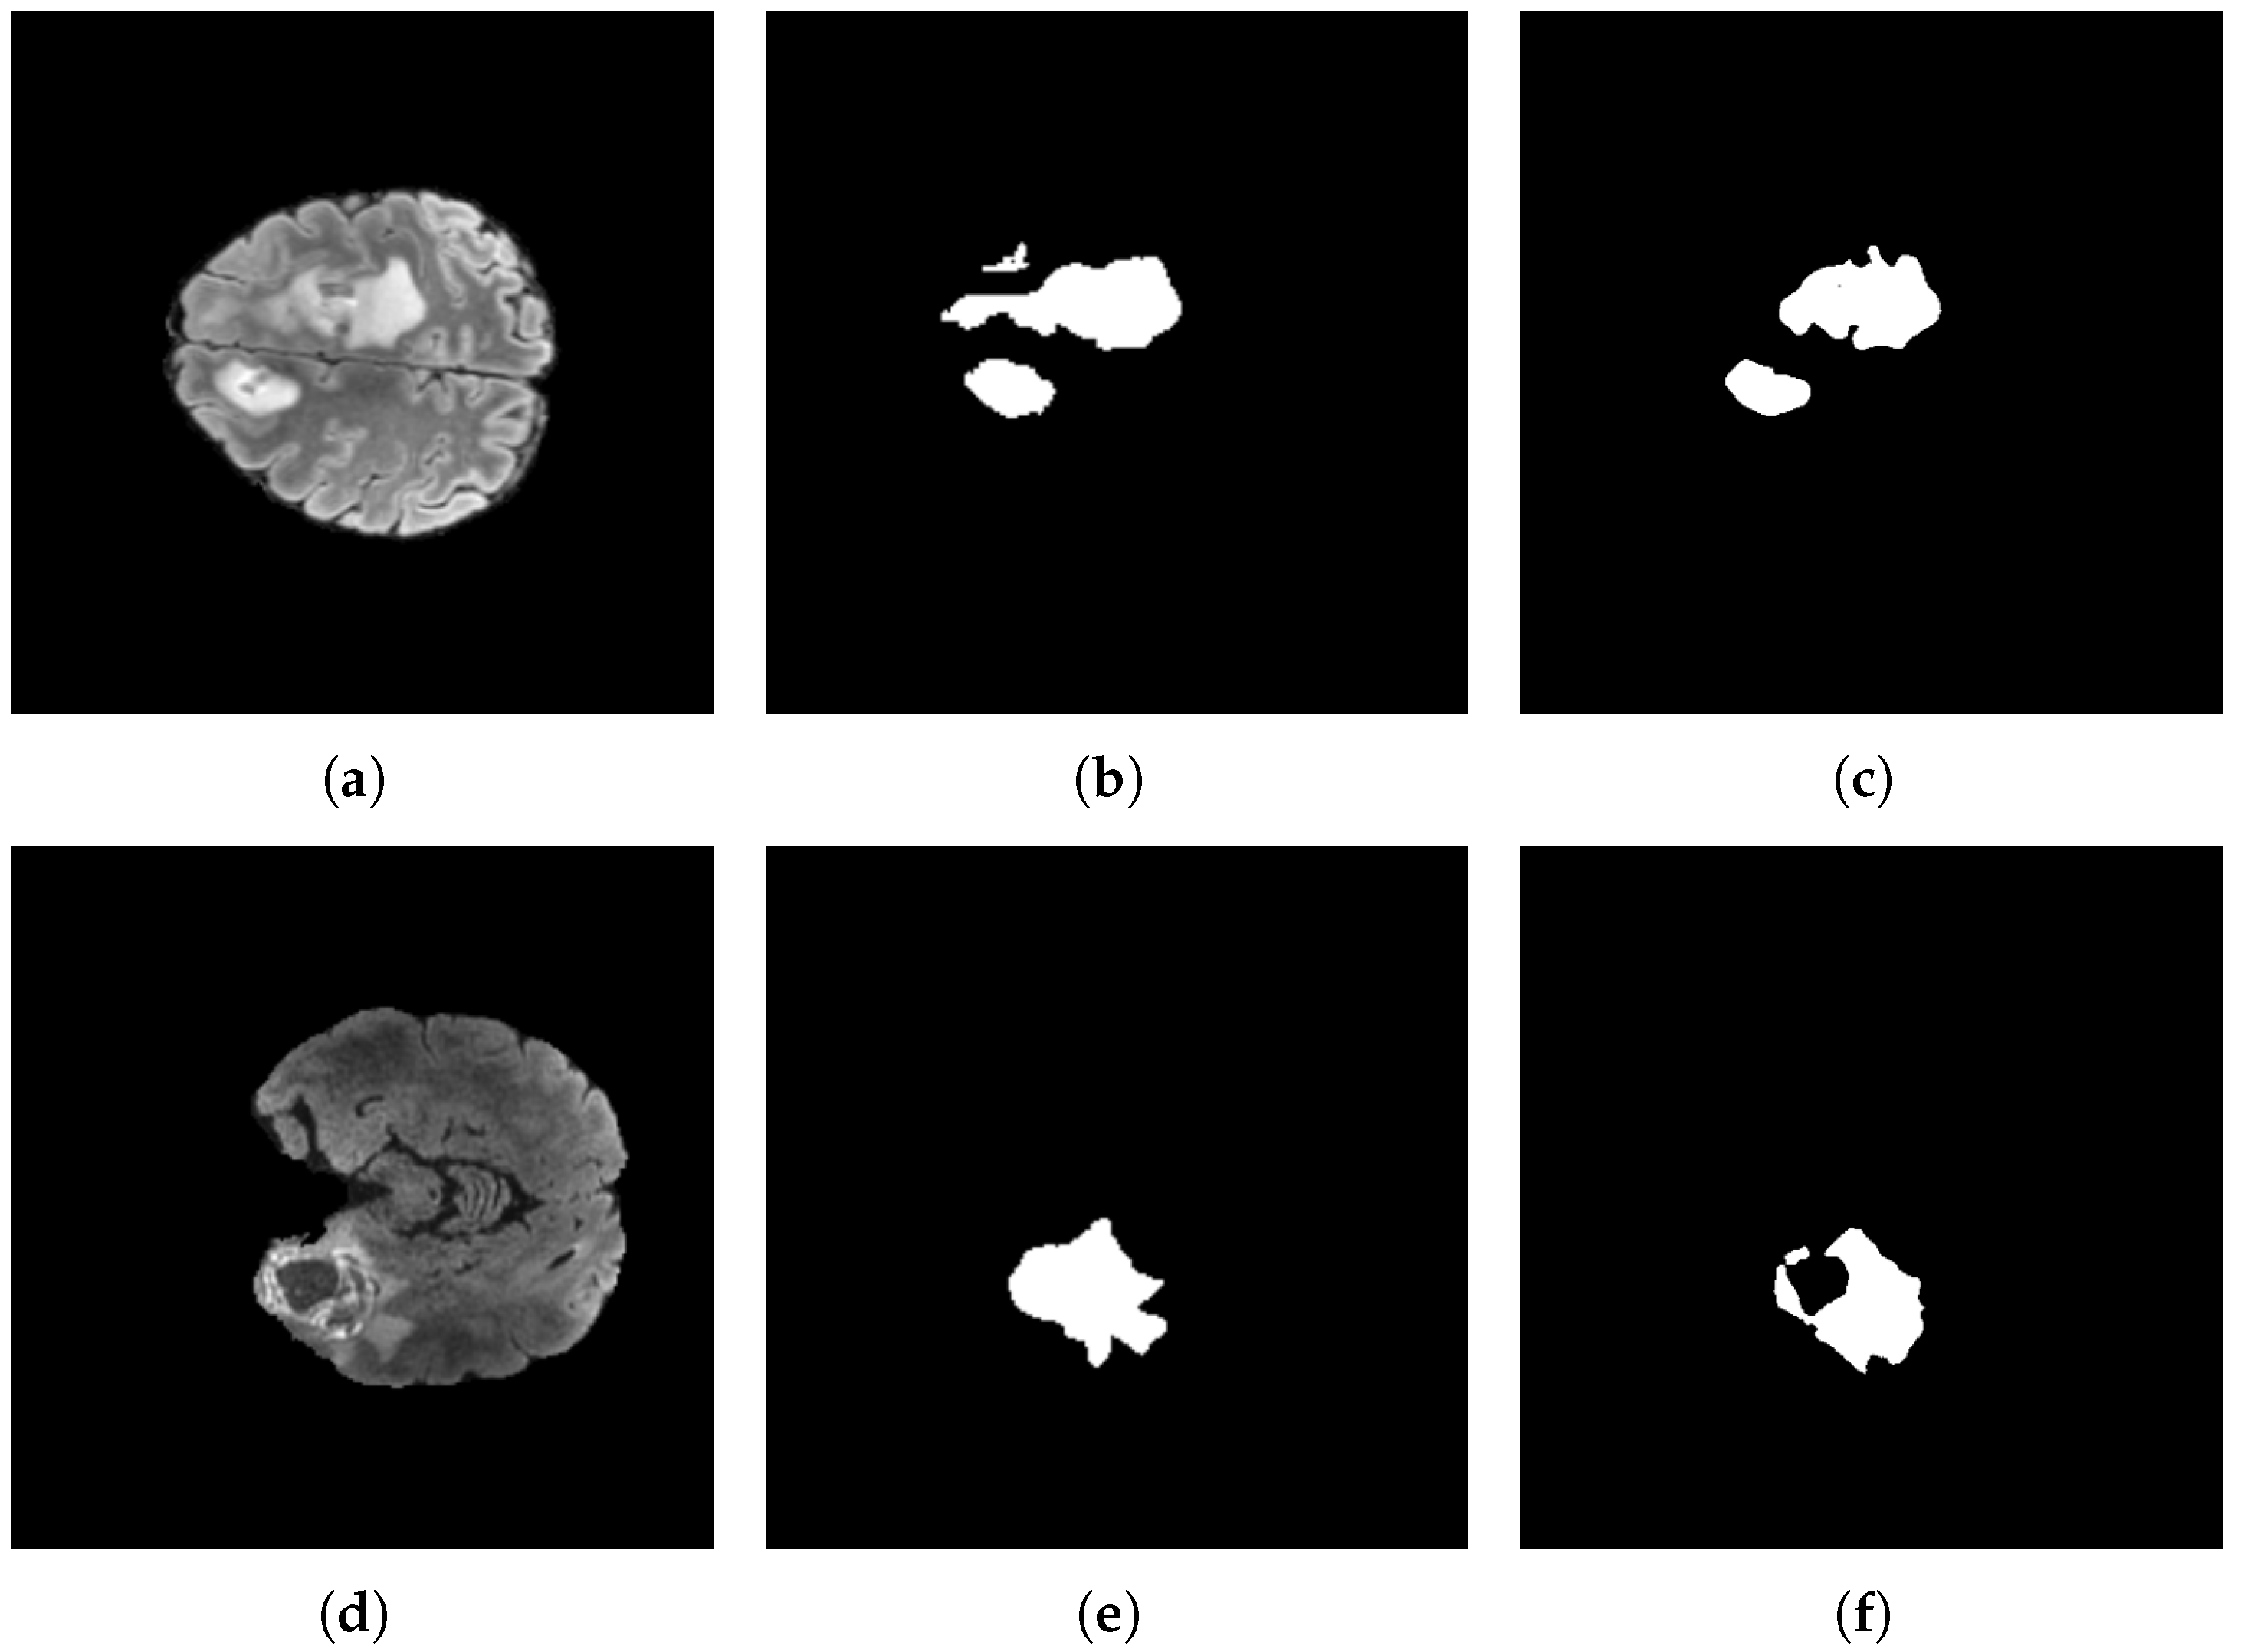

By contrast, Figure 17 presents low-rate recognition cases in which the model’s predictions are suboptimal. Although a non-negligible portion of the lesion is correctly highlighted, relevant regions remain missed. Notably, the errors predominantly manifest as conservative under-segmentation rather than false positives, with no spurious activations in unrelated tissue. This pattern suggests a bias toward precision over recall in these instances.

Figure 18 depicts representative segmentation results on the BraTS 2024 dataset. Specifically, the first row displays the original input images, the second row shows the corresponding ground-truth masks, and the third row illustrates the predictions generated by the proposed model. Figure 18e presents a case featuring two lesions with irregular spiculated margins. The model demonstrates precise segmentation of both structures in Figure 18i, highlighting its ability to delineate multifocal tumors that accurately exhibit significant morphological heterogeneity.

Figure 18f shows the ground-truth image of a single, compact lesion with a broadly rounded contour, whereas Figure 18j presents the corresponding prediction. The model preserves the global extent and topological coherence, producing a single contiguous mask with few components and smooth, well-aligned boundaries. Figure 18g shows the ground-truth image of an irregular lesion, whereas Figure 18k presents the corresponding prediction. The model preserves location and connectivity but exhibits moderate peripheral under-segmentation, most notably along the superior–right margin, where small lobulations in the annotation are omitted, and the predicted boundary is slightly pulled inward relative to the ground-truth image.

Figure 18h shows the ground-truth image of an irregular lesion with two narrow extensions, one lateral and one inferior, connected to a compact core. Figure 18l presents the corresponding image prediction, which preserves location and topology, maintaining both extensions.